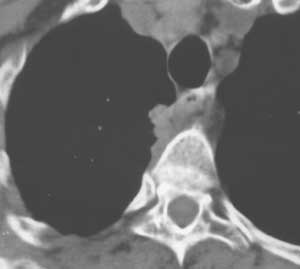

Рис. 9. Кортико-плевральный рак. На компьютерной томограмме четко выявляется бугристая опухоль, тесно связанная с позвонком и врастающая в заднее средостение.